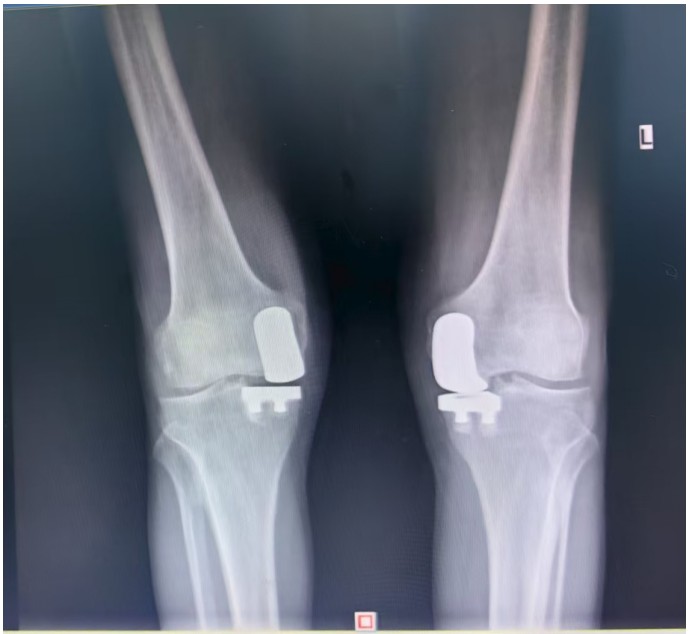

據(jù)了解,患者1年前無明顯誘因出現(xiàn)雙膝關(guān)節(jié)疼痛,以右側(cè)膝關(guān)節(jié)為主,近5個月來雙膝關(guān)節(jié)疼痛明顯加重,不但日常行走困難,生活質(zhì)量更是受到極大影響。經(jīng)多家醫(yī)院治療效果均不理想,了解到衡陽市中心醫(yī)院關(guān)節(jié)外科在關(guān)節(jié)置換領(lǐng)域擁有豐富的臨床經(jīng)驗(yàn)和良好的患者口碑,毅然決定赴衡求醫(yī)。醫(yī)生發(fā)現(xiàn)患者雙膝關(guān)節(jié)已有內(nèi)翻畸形,關(guān)節(jié)內(nèi)側(cè)骨性膨大,X線提示雙膝退行性病變,雙膝內(nèi)側(cè)間隙明顯狹窄,手術(shù)為最佳治療方式。為了達(dá)到根治目的,羅湘平主任醫(yī)師、彭健副主任醫(yī)師為患者進(jìn)行了詳細(xì)查體及綜合評估,術(shù)前組織開展多學(xué)科討論(MDT)。考慮到易叔叔的膝關(guān)節(jié)骨關(guān)節(jié)炎僅局限于內(nèi)側(cè),外側(cè)間室軟骨良好,若采用全膝關(guān)節(jié)置換術(shù)會將失去正常關(guān)節(jié)間室的軟骨與韌帶,創(chuàng)傷較大,便為其制定了右膝關(guān)節(jié)單髁置換手術(shù)治療方案。在充分完善術(shù)前準(zhǔn)備后,羅湘平主任、彭健副主任醫(yī)師團(tuán)隊(duì)為患者實(shí)施了右側(cè)膝關(guān)節(jié)單髁置換術(shù)。手術(shù)過程順利,團(tuán)隊(duì)?wèi)?yīng)用微創(chuàng)術(shù)式(MIS)及“精準(zhǔn)間隙平衡技術(shù)”,最大程度減少了手術(shù)創(chuàng)傷,為術(shù)后快速康復(fù)奠定了堅(jiān)實(shí)基礎(chǔ),術(shù)后第二天即可借助助行器下地活動。6天后團(tuán)隊(duì)順利為患者實(shí)施了左側(cè)膝關(guān)節(jié)單髁置換手術(shù)。目前,易叔叔在關(guān)節(jié)外科醫(yī)護(hù)團(tuán)隊(duì)的精心指導(dǎo)和康復(fù)治療下,恢復(fù)情況良好,雙側(cè)膝關(guān)節(jié)活動度輕松達(dá)到90°,膝關(guān)節(jié)功能顯著改善,能夠獨(dú)立下地行走,對手術(shù)效果非常滿意,已于9月10日順利出院。

羅湘平主任介紹,膝單髁置換術(shù)是針對膝關(guān)節(jié)單側(cè)間室病變的微創(chuàng)手術(shù),該術(shù)式通過置換單側(cè)股骨或脛骨受損軟骨表面,保留交叉韌帶及正常骨質(zhì)結(jié)構(gòu),因創(chuàng)傷小、恢復(fù)快被稱為膝關(guān)節(jié)置換中的“補(bǔ)牙”技術(shù),適用于單間室骨關(guān)節(jié)炎且韌帶功能完整的患者。膝關(guān)節(jié)單髁置換為特定的膝關(guān)節(jié)疾病患者提供了一種較為理想的治療選擇,它以較小的手術(shù)創(chuàng)傷、良好的術(shù)后功能恢復(fù)效果,幫助患者緩解疼痛,恢復(fù)正常的生活和活動能力。